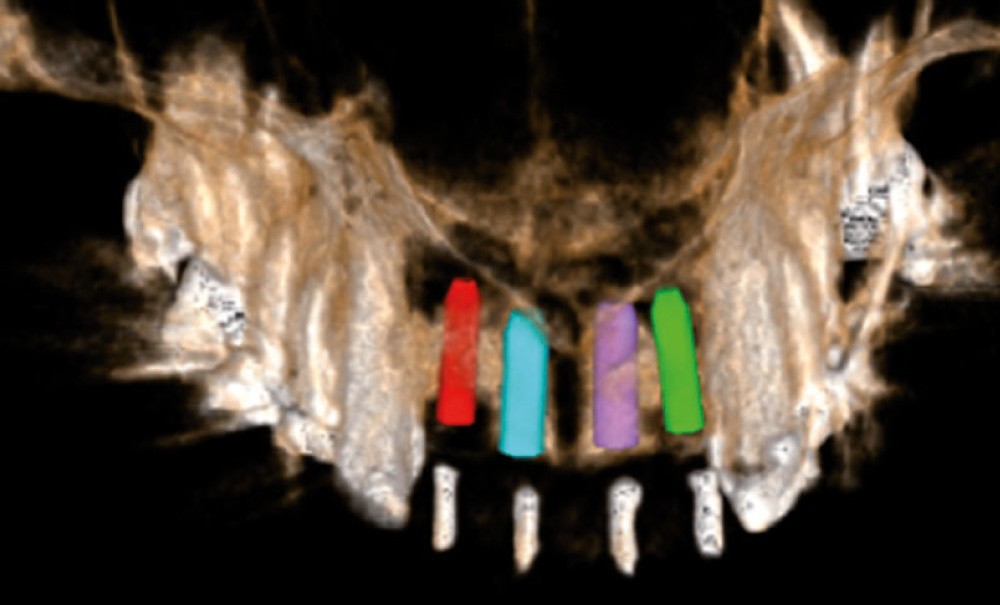

L’examen endobuccal montre deux fistules en regard des apex de 12 et 21 (fig. 1). Nous notons la présence d’une classe III squelettique, d’une occlusion inversée du côté droit (fig. 2) et des édentements non compensés au niveau de 26 et 36. L’orthopantomogramme révèle la présence d’une volumineuse lésion kystique qui s’étend de la 12 à la 22 (fig. 3).

Une imagerie 3D est réalisée…